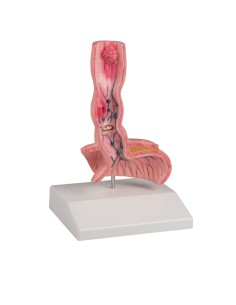

Dal cranio in 22 parti con incastri magnetici ai modelli di colonna vertebrale, da quelli di articolazioni a quelli di cuore, ogni pezzo della nostra collezione è progettato per un’immersione totale nello studio dell’anatomia umana. I nostri modelli, realizzati tramite scansioni di ossa vere, garantiscono un’esperienza tattile autentica e una fedeltà di peso quasi identica agli originali.

Essenziali per studenti e professionisti, i nostri modelli anatomici sono strumenti didattici che permettono di osservare le strutture anatomiche con precisione, eliminando la necessità di dissezioni o studi invasivi. Sono inoltre utili per spiegare ai pazienti le patologie, rendendo la comunicazione più efficace e risparmiando tempo prezioso.